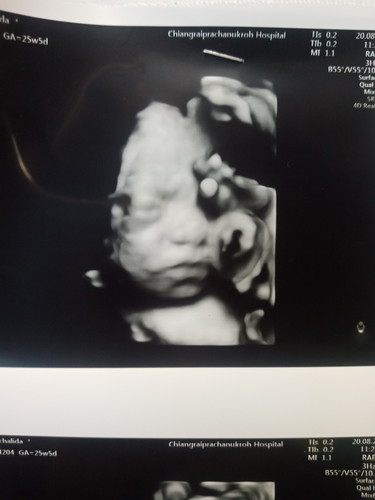

วันนี้คุณหมอนัด ได้ซาว4Dครั้งแรกตื่นเต้นมากค่ะ ได้เห็นหน้าลูกแบบชัดเจนมาก คุณหมอบอกเหมือนแม่มาก ได้26wแล้วลูกชายแม่ ขอดูของบ้านอื่นหน่อยค๊าา??

ซาวด์4มิติตอน28w ลูกสาวจ้า ปัจจุบันคลอดน้องได้จะ4เดือนแล้วจ้า